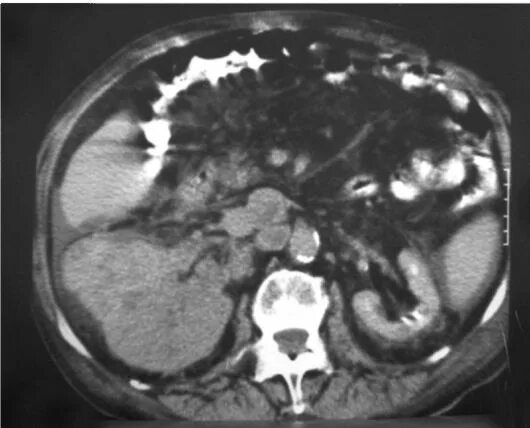

50 лет кт